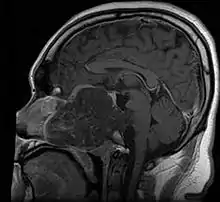

Anatomy

- In adults, remnants of notochord are present as the nucleus pulposus of the intravertebral discs, and distribution of tumors matches distribution of the remnants

- ~35% in sphenooccipital region (almost always involving clivus)

- 15-30% in vertebral column

- 30-50% in sacrococcygeal region

- Skull base:

- May be intracranial or extracranial, with mass effect symptoms depending on location

- Headaches and/or facial pain are common

- Pituitary insufficiency, hemianopsia/diplopia, cranial nerve deficits, nasal stuffiness.